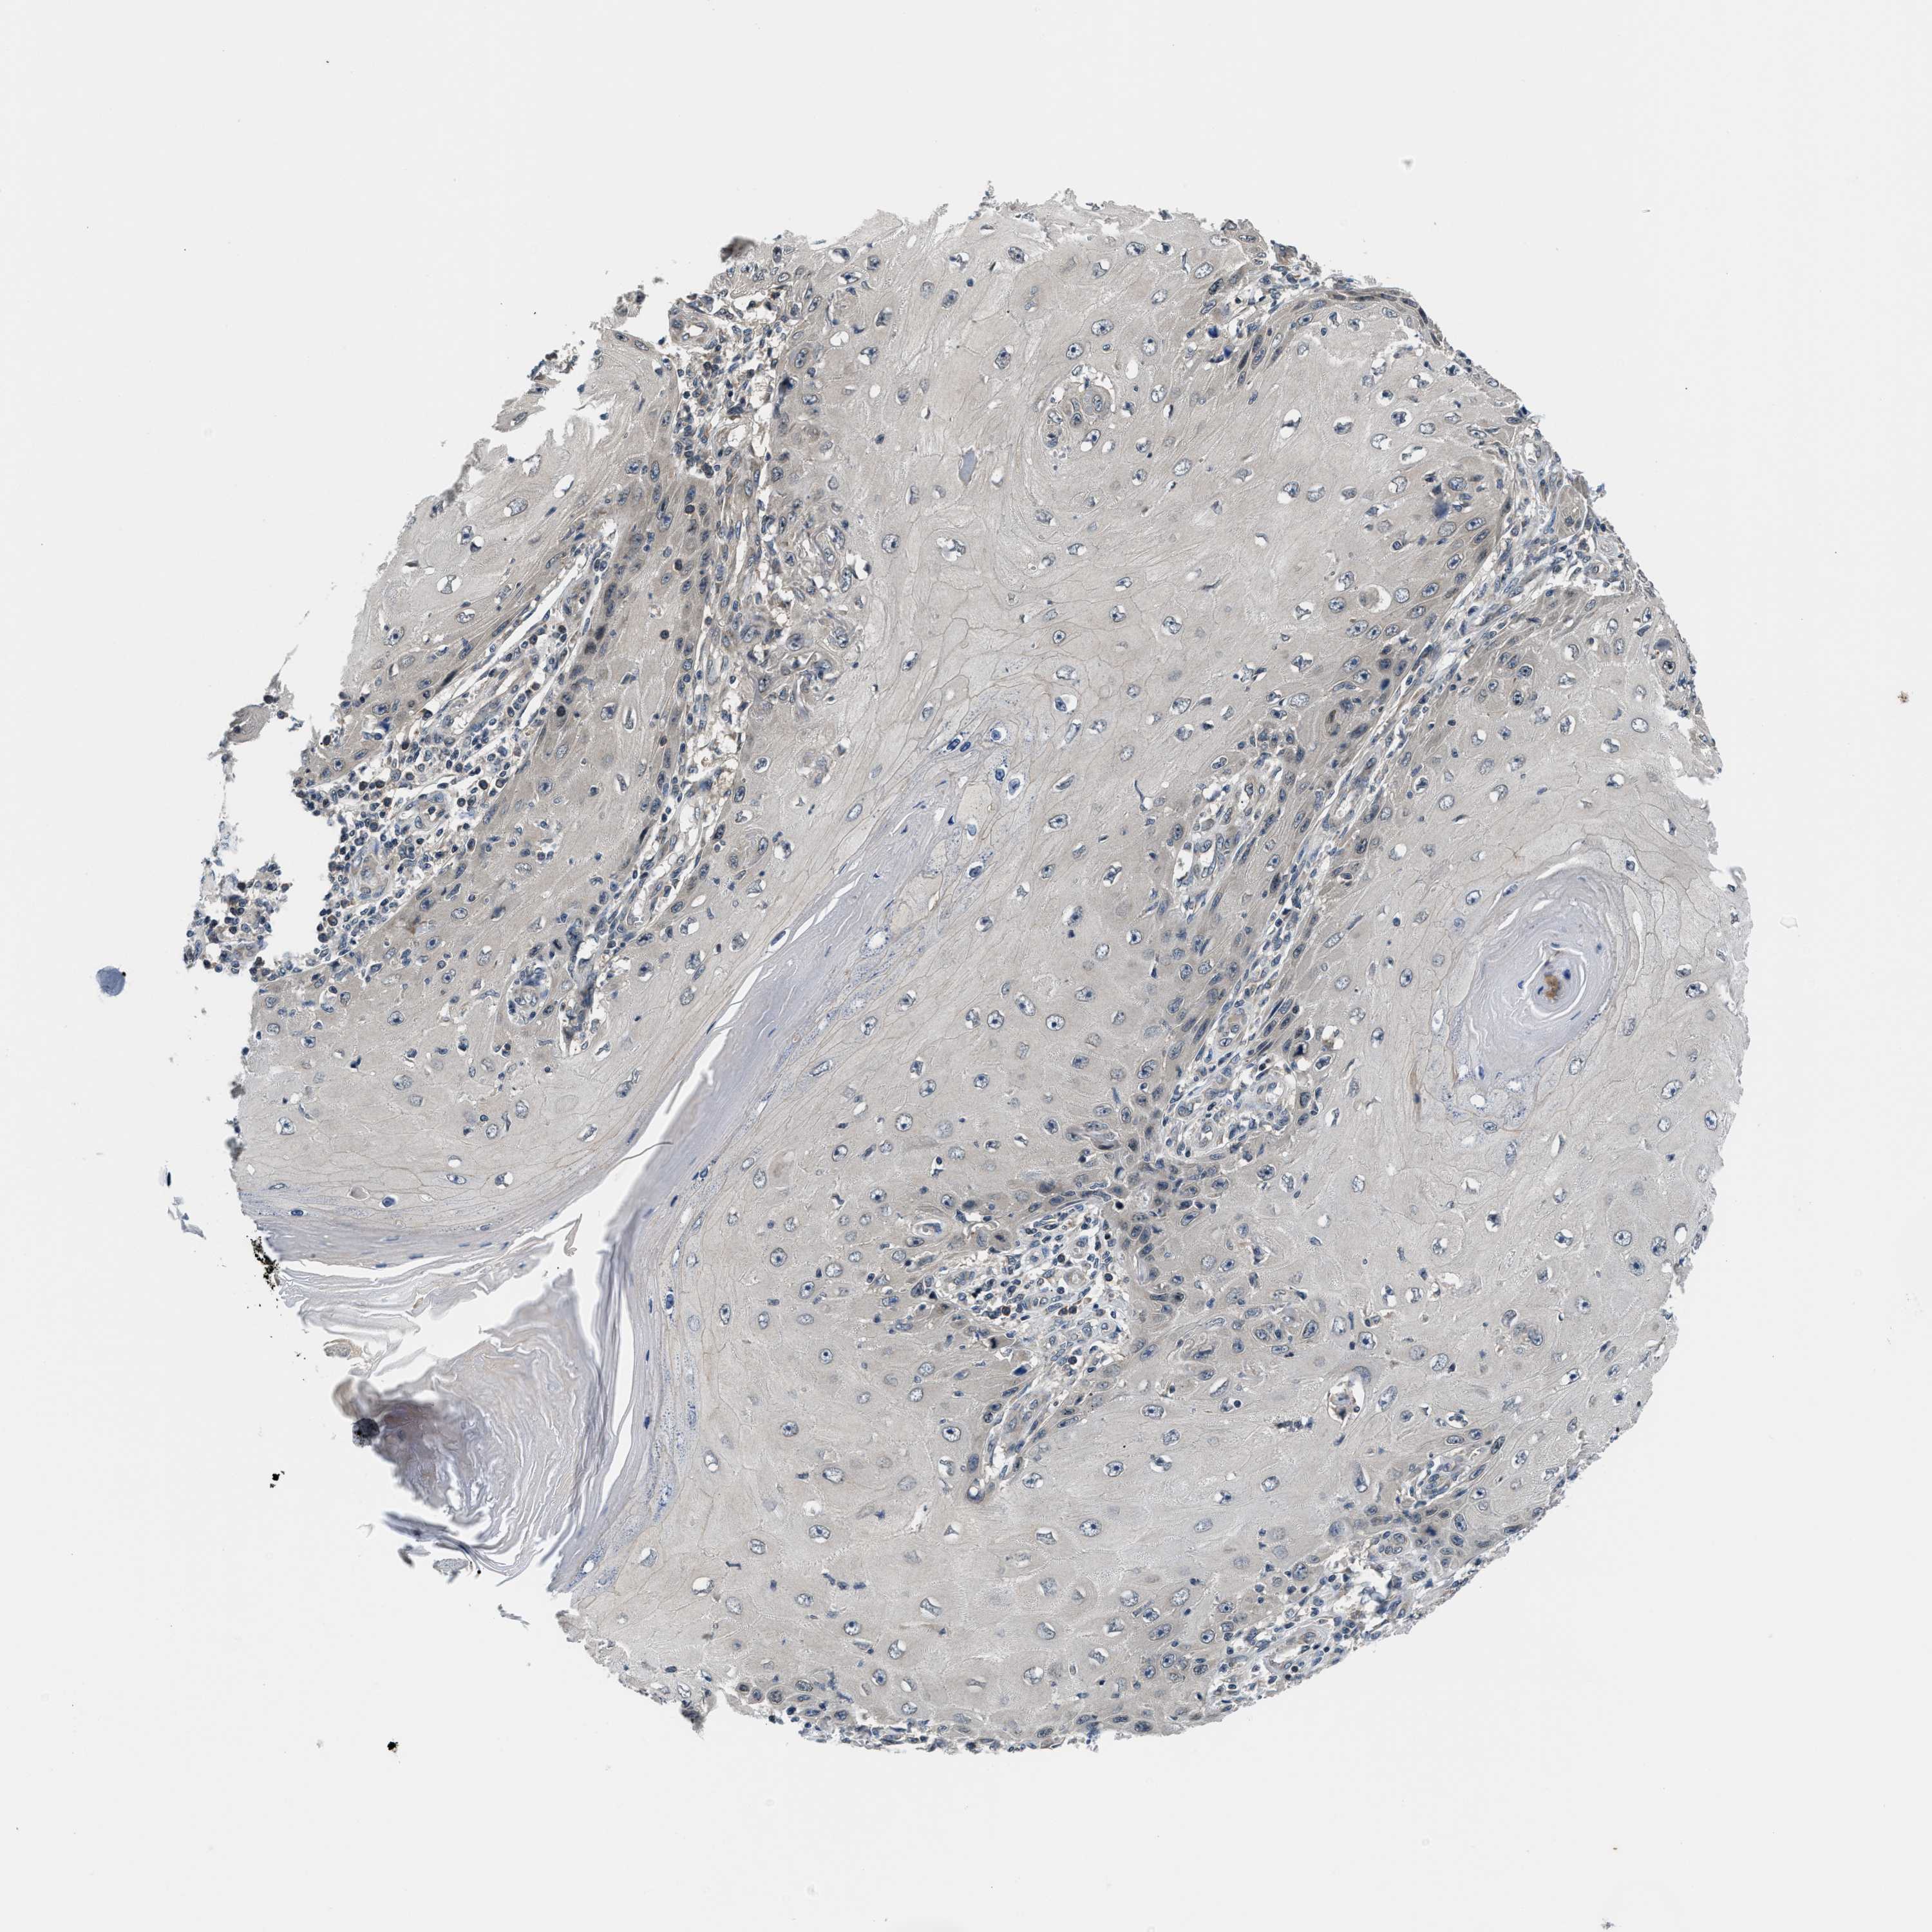

SKIN CANCER - Protein expressioni

A mouse-over function shows sample information and annotation data. Click on an image to view it in a full screen mode. Samples can be filtered based on level of antibody staining by selecting one or several of the following categories: high, medium, low and not detected. The assay and annotation is described here.

Each image is clickable and will lead to virtual microscopy that enables deeper exploration of all samples and also displays staining intensity scores, fraction scores and subcellular localization as well as patient and tissue information for each sample.

Antibody CAB020822

Medium

Moderate

75%-25%

Nuclear

Squamous cell carcinoma, NOS